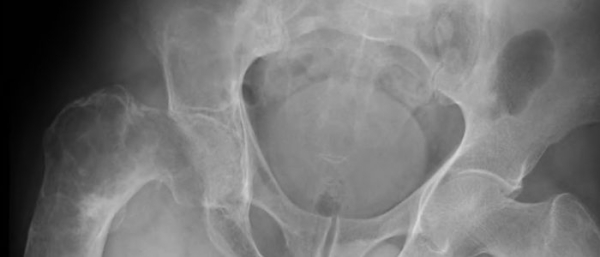

Фиброма яичника — доброкачественная опухоль, состоящая из соединительной ткани. Каждая 10-я женщина становится обладательницей недуга. Зачастую фибромы яичника появляются в возрасте от 40 до 60 лет, но возможны и более ранние случаи. В основном проявляется в одном из яичников (правом или левом). Отличается круглой или овальной формой с четкими границами. Размеры фибромы варьируются в диапазоне 1−12 см в диаметре. Отличительная особенность — при фиброме отсутствует активная выработка гормона, что характерна для других образований. Диагностировать проблему можно с помощью специального оборудования, визуальных проявлений она не имеет. Вызывают опасность и болевые ощущения по мере роста, затрагивая и сдавливая близлежащие органы и ткани. Фиброма относится к группе с низким риском перерастания в злокачественную опухоль.

Страдают фактически все функции организма. Сама по себе фиброма круглая, без капсулы для сбора жидкости. Располагается опухоль на ножке, за счет этого подвижна при пальпации. Края фибромы четкие, не размытые, с ровной или узелковатой поверхностью. Консистенция образования плотная и эластичная. В зависимости от наличия тканей имеет мягкую или твердую структуру. Ниже приведена таблица с классификацией видов фибром правого или левого яичника.

Первым этапом в диагностике есть визуальный осмотр образования на гинекологическом кресле, пальпация и устный опрос. Это дает возможность определить само наличие проблемы и распознать ощущения пациента, с нею связанные. Также поможет выяснить возможные причины, повлекшие проблему. Для более детальной картины заболевания проводят УЗИ с красящим веществом (цветное допплеровское картирование). При этом определяется размер, форма и структура образования, а также специфика кровоснабжения опухоли. В дополнение или как самостоятельную методику диагностирования можно применять МРТ и КТ. Гистологическое исследование на наличие раковых клеток проводят с удаленного материала, после операции.